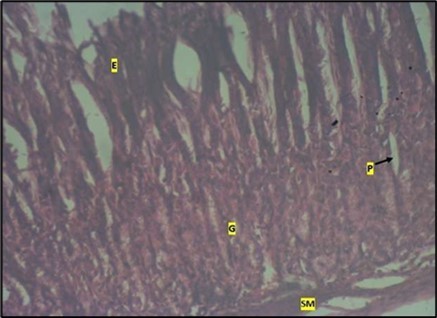

Micrographs of The Stomach

Histological examination of the stomach in control animals showed normal appearance of epithelial cells lining the mucosa and normal smooth muscles in the submucosa (Figure 8). However, administration of Abelmoschus esculentus at low dose showed deep epithelial gastric area with marked depletion of pits and goblet cells (circled area) and normal smooth muscles in the submucosa (Figure 9) and the high dose group showed dysplasia of gastric pits with goblet cells in the mucosa and the smooth muscles in the submucosa were mildly eroded (Figure 10).

Figure 8.control plate showing gastric pits with goblets cells (g). Smooth muscle layer (SM) and surface epithelium (e) appears normal. (H&E).

Figure 9.Image showing deep epithelial gastric pit area with marked depletion of pits and goblet cells (circled area). Smooth muscle (sm) appears normal in animals treated with Low dose of Abelmoschus esculentus stained with H & E technique X100

Figure 10.Image of a wistar rats stomach treated with high dose of abelmoschus esculentus showing dysplasia of gastric pits with the arrows mark (p). Goblet cells mark with arrow (g) appear at the basal mucosa and smooth muscle (sm) appear mildly eroded. The slide was stained using h & e technique. X100